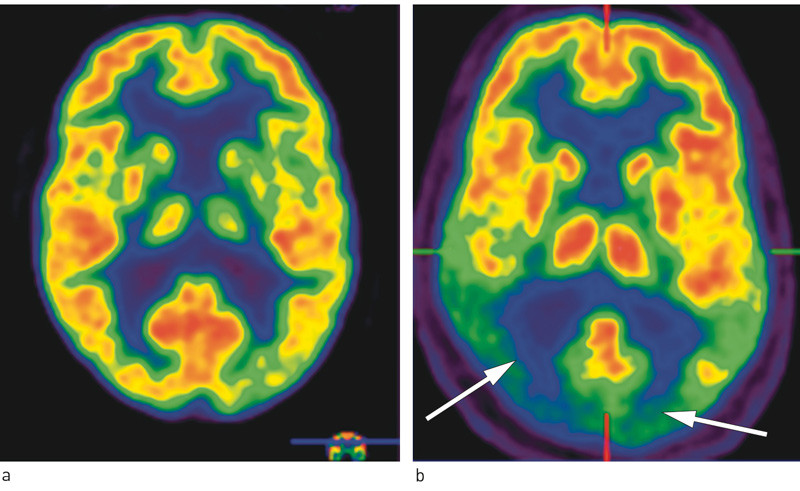

Genvarianten apolipoprotein E4 (apoE4) er assosiert med økt risiko for Alzheimers sykdom. Det er observert økt frekvens av apoE4 hos pasienter med posterior kortikal atrofi i noen store studier (18, 20), mens noen mindre studier har vist lavere forekomst av apoE4-allelet (21). Cerebral MR-undersøkelse kan være normal i tidlig fase. Senere i forløpet kan man se kortikal atrofi parieto-oksipitalt, som regel mer uttalt i høyre enn i venstre hemisfære (22). Hvis MR-funn ikke gir grunnlag for diagnosen, kan positronemisjonstomografi (PET) med radioaktiv glukose-analog (18FDG) vise nedsatt metabolisme i bakre deler av de cerebrale hemisfærer (13) (fig 1). Hypometabolismen er gjerne mest uttalt i høyre hemisfære.

I en sammenlikning med friske kontrollpersoner fant Nestor og medarbeidere at det ved posterior kortikal atrofi også var frontal hypometabolisme dorsolateralt bilateralt, svarende til de frontale øyefeltene. Dette funnet ble tolket som uttrykk for manglende input fra oksipito-parietale områder til frontalcortex (13). De frontale øyefeltene er essensielle for raske voluntære øyebevegelser, og de mottar viktig input fra de visuelle assosiasjonsområdene. Forstyrrelse av denne forbindelsen er én mulig årsak til okulomotorisk apraksi hos pasienter med posterior kortikal atrofi (13).

Enfotonemisjonstomografi (SPECT) viser hjernens blodgjennomstrømming og påviser i prinsipp de samme utfallene som 18FDG-PET, siden blodforsyning og glukosemetabolisme er nær knyttet til hverandre. Vår egen erfaring med denne pasientgruppen taler for å bruke FDG-PET hvis metoden er tilgjengelig, fordi den fremstiller det typiske metabolismemønsteret ved posterior kortikal atrofi tydeligere enn SPECT-metoden gjør.